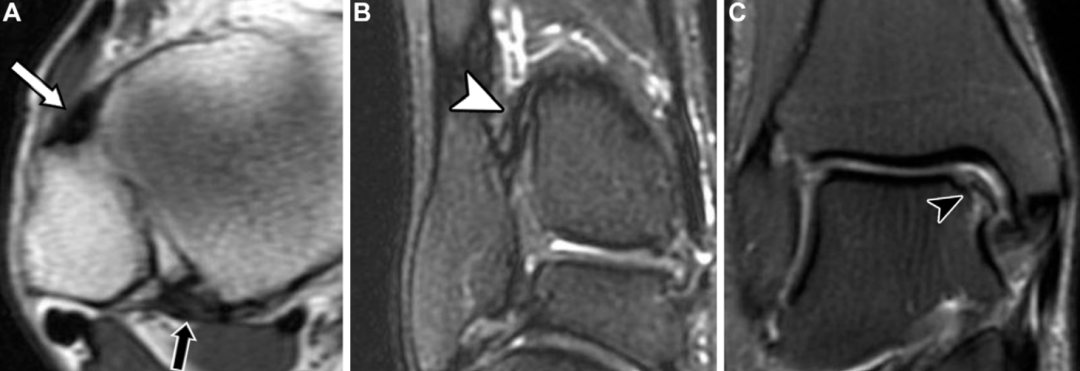

MRI是评估急性远端胫腓联合损伤的金标准影像学方法,据报道,其诊断前下胫腓韧带撕裂的准确率为76%~100%,诊断后下胫腓韧带撕裂的准确率为 88%~100%。MRI上,完整的胫腓联合韧带在所有脉冲序列中均表现为低信号的条带状结构。与其他韧带结构相同,根据影像学表现,胫腓联合韧带损伤可分为轻度扭伤、部分撕裂(中度扭伤)和完全撕裂(重度扭伤):扭伤表现为韧带增厚、信号增高及周围水肿;部分撕裂表现为韧带内局灶性连续性中断;完全撕裂则表现为韧带全层连续性中断或韧带缺如。

下胫腓前韧带和下胫腓后韧带与正交平面呈斜行走向,在常规轴位MRI上可能被误判为撕裂。常规踝关节斜轴位MRI序列的扫描平面,需在矢状位定位像上垂直于腓骨肌腱,沿肌腱从踝后至足中段的走行方向设定。本文作者认为,该序列有助于评估下胫腓前韧带和下胫腓后韧带,对下胫腓前韧带的评估效果尤为显著:

三维各向同性涡轮自旋回波序列为评估远端胫腓联合提供了可靠方法,该序列具有高信噪比和对比噪声比,可进行多平面重建,包括45°斜位评估,其对急、慢性胫腓联合损伤的诊断效能与二维质子密度加权MRI相当。尽管三维SPACE序列(基于不同翻转角演化的优化对比采样完美序列)的图像边缘清晰度低于二维涡轮自旋回波序列,但其能清晰显示韧带的连续性、轮廓和信号强度,可实现准确诊断,对急性损伤的诊断尤为适用;对于慢性损伤,斜位成像可提升韧带形态的显示效果,有助于损伤分型。